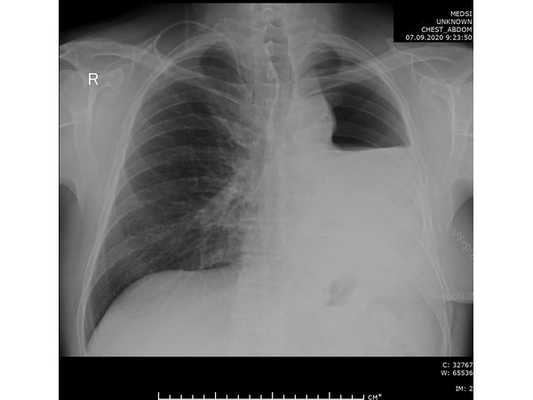

При дальнейшем дообследовании, по данным рентгенографии и компьютерной томографии органов грудной клетки выявлено новообразование в нижней доле левого лёгкого. После этого пациент был направлен на консультацию к торакальному онкологу.

Чтобы провести первичное стадирование опухоли, пациенту проведена позитронно-эмиссионная томография в сочетании с компьютерной томографией (ПЭТ-КТ). По данным исследования, выявлена метаболически активная опухоль в корне левого лёгкого с бугристыми контурами размерами 41 х 43 мм. В толще опухоли проходят нижнедолевой бронх и бронх 6-го сегмента левого лёгкого, просветы бронхов значительно сужены. Нижняя доля левого лёгкого уменьшена в размерах за счёт того, что сегменты 6, 9 и 10 субтотально (частично) инфильтрированы и безвоздушны. Лимфатические узлы корня лёгкого и средостения не увеличены в размерах и не накапливают радиофармпрепарат (РФП), который был введён пациенту перед обследованием внутривенно. Других очаговых образований и очагов гиперметаболизма в организме не обнаружено.

При этом отмечено, что опухоль распространяется в средостение по нижней стенке левого главного бронха и широко прилежит к нижнегрудному отделу аорты (по заключению специалиста ПЭТ-КТ — имеется инвазия опухоли в ткани средостения и возможное врастание в стенку аорты). При самостоятельном пересмотре изображений отмечено, что "опухолевая" ткань, которая распространяется по нижней стенке левого главного бронха в средостение, не накапливает РФП (т. е. не является злокачественной), а стенка аорты в области "инвазии" опухоли имеет ровный чёткий контур и адвентициальную границу, что также свидетельствует об отсутствии онкологического процесса в этой области.

Проведена профилактическая стандартная антибактериальная терапия в течение пяти суток. По данным контрольной рентгенографии, отмечено смещение средостения в оперированную сторону.